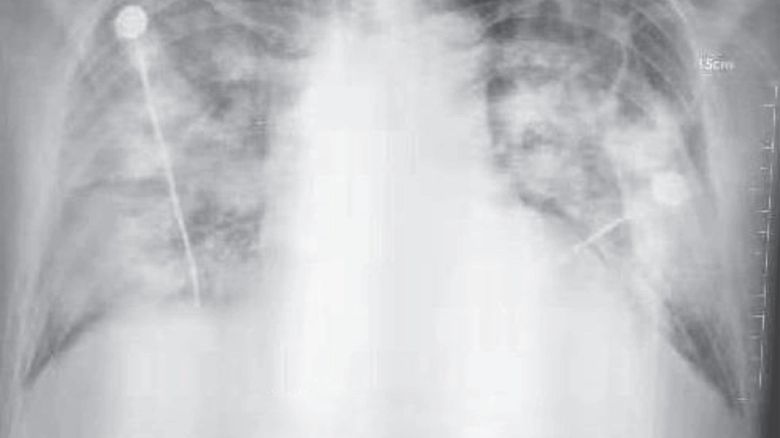

▲ 우한 폐렴 환자의 흉부 방사선 사진

(사진=NEJM 논문 발췌, 연합뉴스)